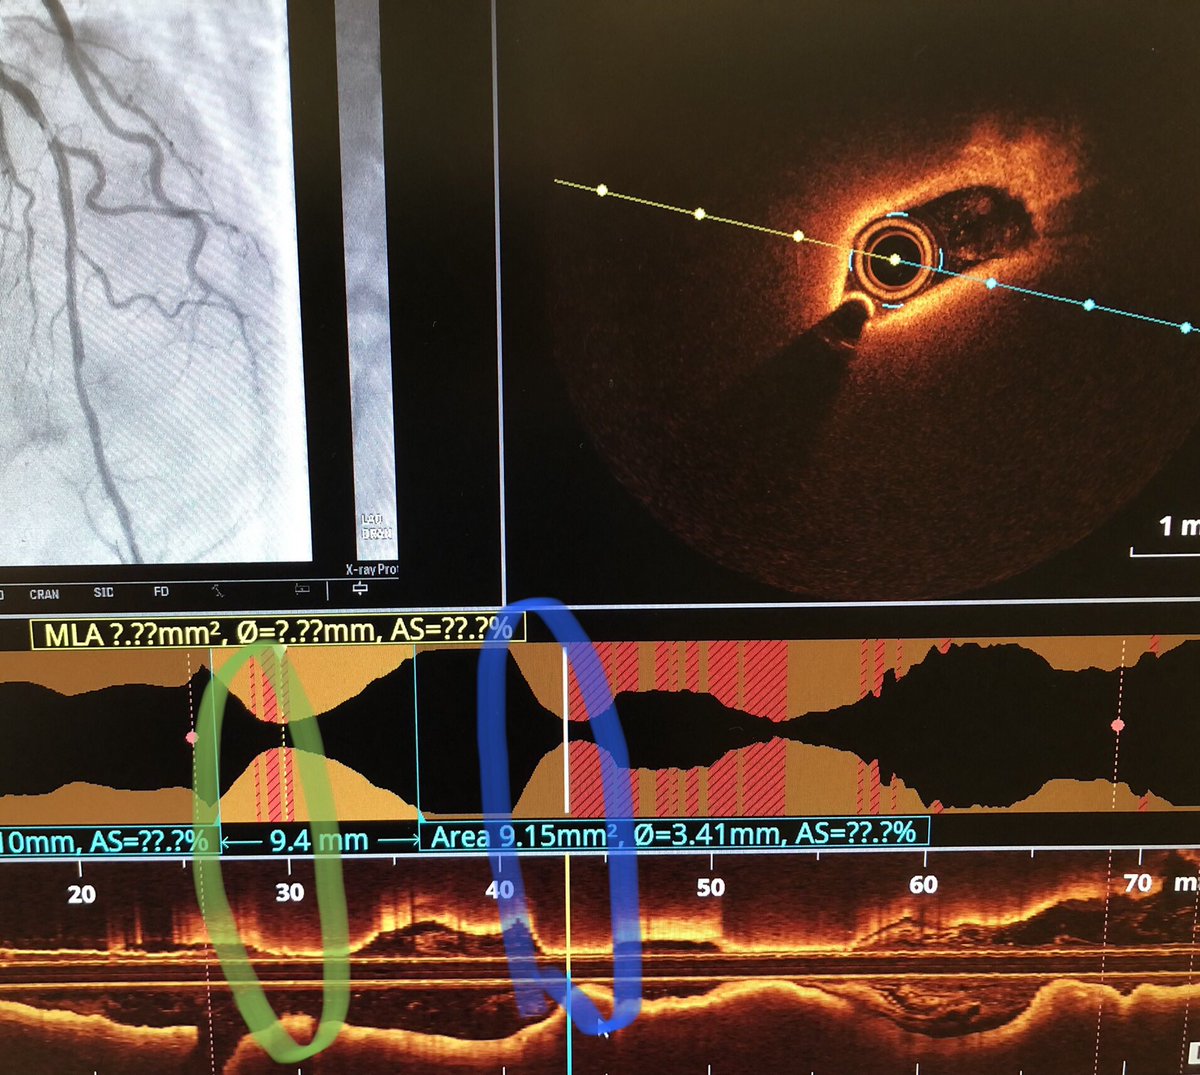

OCT conundrum 🤔 OCT run of this mid-LAD lesion (Fig 1) confirms tight stenosis (circled green) But where did these other two surprise lesions (circled blue) come from ???? #RadialFirst